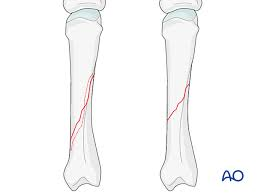

• Oblique Fracture

a fracture that occurs at an angle to the bone's axis